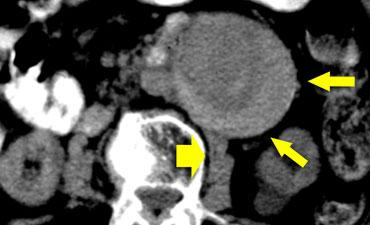

Dấu hiệu liềm tăng tỷ trọng ở bệnh nhân có bằng chứng rò rỉ nhẹ tiếp giáp cơ thắt lưng phải (mũi tên rộng).

Liềm tăng tỷ trọng

Hình ảnh liềm tăng tỷ trọng đại diện cho khối tụ máu cấp tính nằm trong huyết khối thành mạch hoặc thành túi phình.

Dấu hiệu này có liên quan chặt chẽ với vỡ phình động mạch chủ bụng.

Độ nhạy của dấu hiệu liềm tăng tỷ trọng như một chỉ điểm của phình động mạch chủ có biến chứng là 77%; độ đặc hiệu 93%; và giá trị tiên đoán dương tính 53%.

Do đó, ngay cả khi không có dấu hiệu vỡ chính, chúng ta vẫn cần thông báo cho bác sĩ lâm sàng rằng bệnh nhân này có nguy cơ rất cao bị vỡ phình động mạch chủ trong vài ngày tới.

Bên trái là hai trường hợp khác của dấu hiệu liềm tăng tỷ trọng.

Trong trường hợp bên phải, chúng ta cũng có thể xác định được khối tụ máu sau phúc mạc, do đó trong trường hợp này đã có vỡ phình động mạch chủ bụng hoàn toàn.